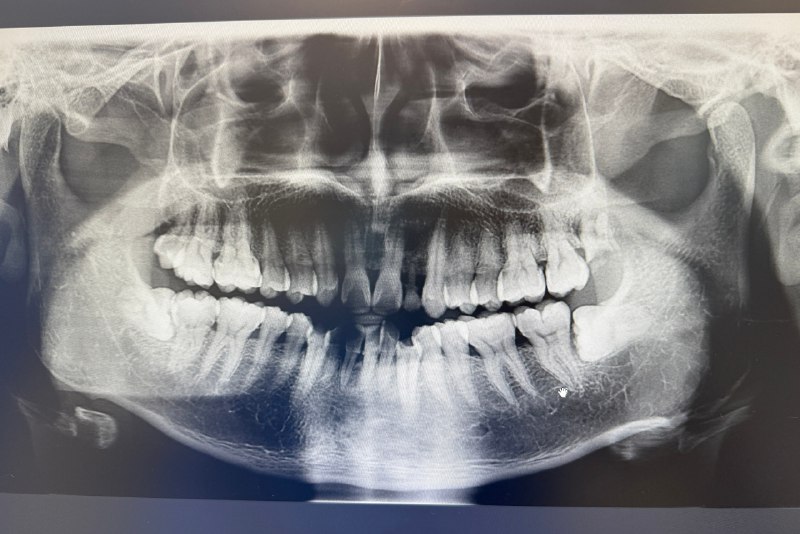

我的牙片

上图是我10月10日拍的牙片,4颗智齿全长出来了。医生看过后,说了两点:

左侧上方那颗,已经蛀掉了,得拔掉

下面2颗,大部分埋在牙龈中,会有些难拔

日常偶尔会出现智齿发炎疼痛,且有蛀牙,所以决定拔掉,计划分两次,第一次拔左边有蛀牙的一侧,第二次拔右边。医生的拔牙预约特别满,等到昨天(11月7日)才安排上。

智齿要不要拔,没有明确的说法,有些情况建议拔除,比如智齿导致牙龈反复发炎,智齿已经蛀牙。拔牙时间20-30岁之间最佳,此时智齿可能还没有特别硬、特别稳固,容易拔,且年轻人,拔除后创伤恢复快。